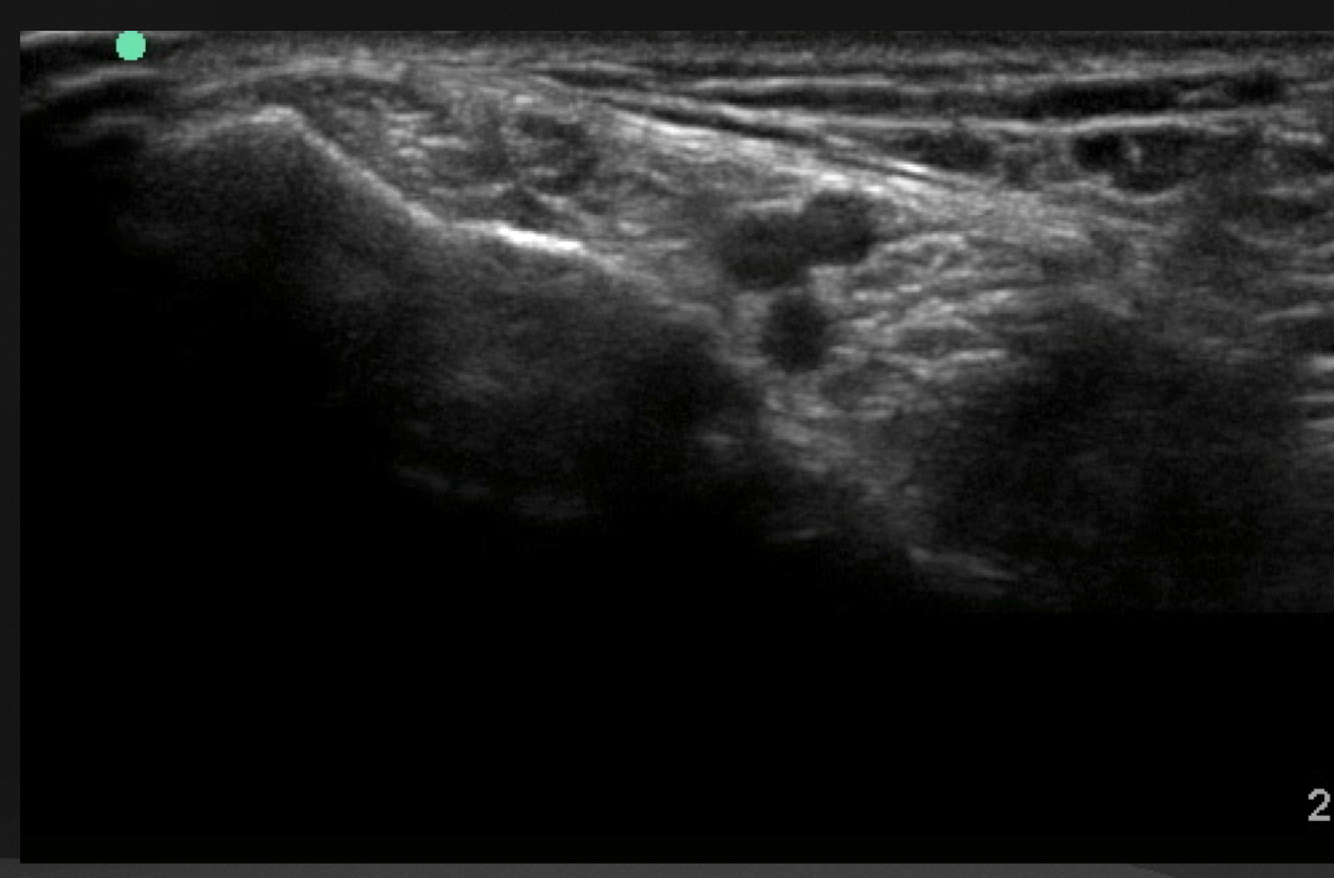

Quoi la pathologie ici?

A

Kyste ganglionnaire intra-neural (où il y a des petites étoiles